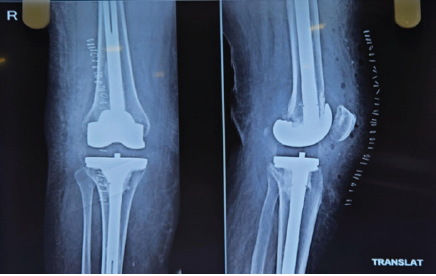

On admission to our center, she had persistent swelling and pain with restricted mobility. A one-stage revision TKR was performed, involving implant removal, extensive synovectomy, and reconstruction with a constrained modular revision system. Intraoperative images, as per Fig. 3, show metallic debris and a worn-out polyethylene liner, which gives us a diagnosis of metallosis. Post-operative radiographs confirmed stable implants without evidence of loosening, as shown in Fig. 4.

Figure 4: Post-operative X-ray following revision total knee replacement of the right knee.